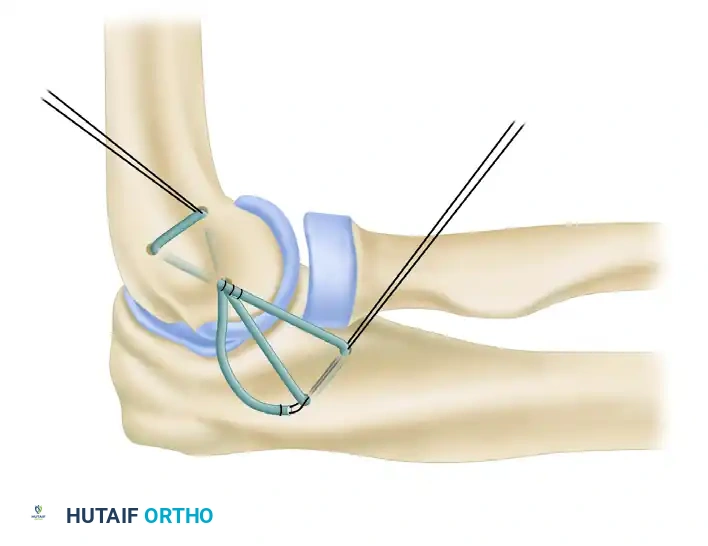

7. Graft Tensioning and Final Fixation

The two limbs of the palmaris longus tendon are drawn proximally and introduced into the humeral tunnels.

* The graft is tensioned with the elbow held in approximately 30 to 40 degrees of flexion and the forearm in full pronation. Pronation is critical as it closes the lateral joint space and reduces the posterolateral subluxation.

* Apply a varus stress to ensure the joint is fully reduced while tensioning.

Once optimal tension is achieved, the palmaris longus tendon limbs are drawn through the ulnar and humeral tunnels and tied to themselves after recrossing the joint. This figure-of-eight or docking configuration provides a robust, anatomic reconstruction of the LUCL. The native capsular flaps and common extensor origin are then meticulously repaired over the graft to provide additional dynamic stability.